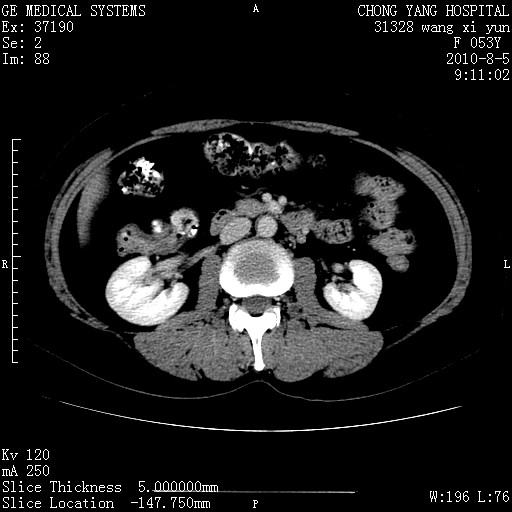

标题: CT28214:F41Y 血尿二十天,建议盆腔平扫加增强。

1)考虑肝左叶胆管细胞癌。2)脂肪肝。